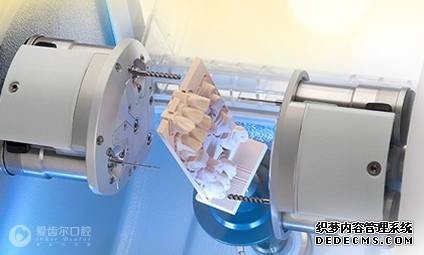

精确打磨

全瓷牙冠制作成型